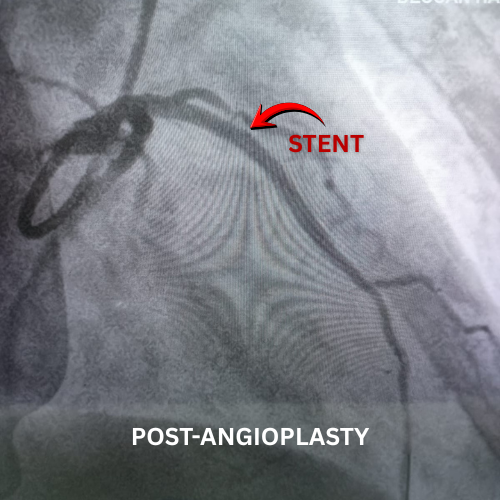

Successful Cardiac Case at Deccan Hardikar Hospital

A 72-year-old female presented with a history of heart attack and severe chest pain. At Deccan Hardikar Hospital, our cardiac team successfully opened her main artery, which was 100% blocked, using a drug-eluting stent. The patient responded well to treatment and recovered successfully.